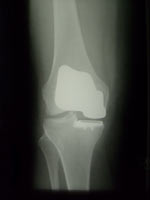

• Endoprothetik

• Verschleiß der Gelenkflächen kann zu einer schmerzhaften Einsteifung, Fehlstellung oder Instabilität des Kniegelenkes führen. Moderne Prothesen ersetzen ein, zwei oder alle drei Gelenkanteile (die Innenseite, die Kniescheibe und ihr Gleitlager, die Außenseite). Die Prothesenteile sind ungekoppelt oder – bei Vorliegen einer Instabilität – achsgeführt und zumeist zementiert.

Zweidrittelprothese Zweidrittelprothese Oberflächenprothese Oberflächenprothese